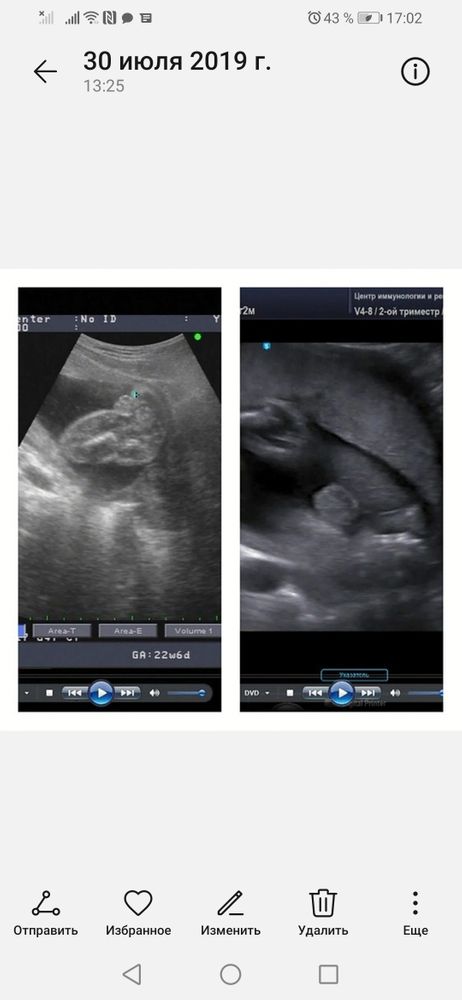

Изображение Слева девочка, справа мальчик, но сроки на обеих фото довольно большие. Ракурс между ножек.

07.10.2022